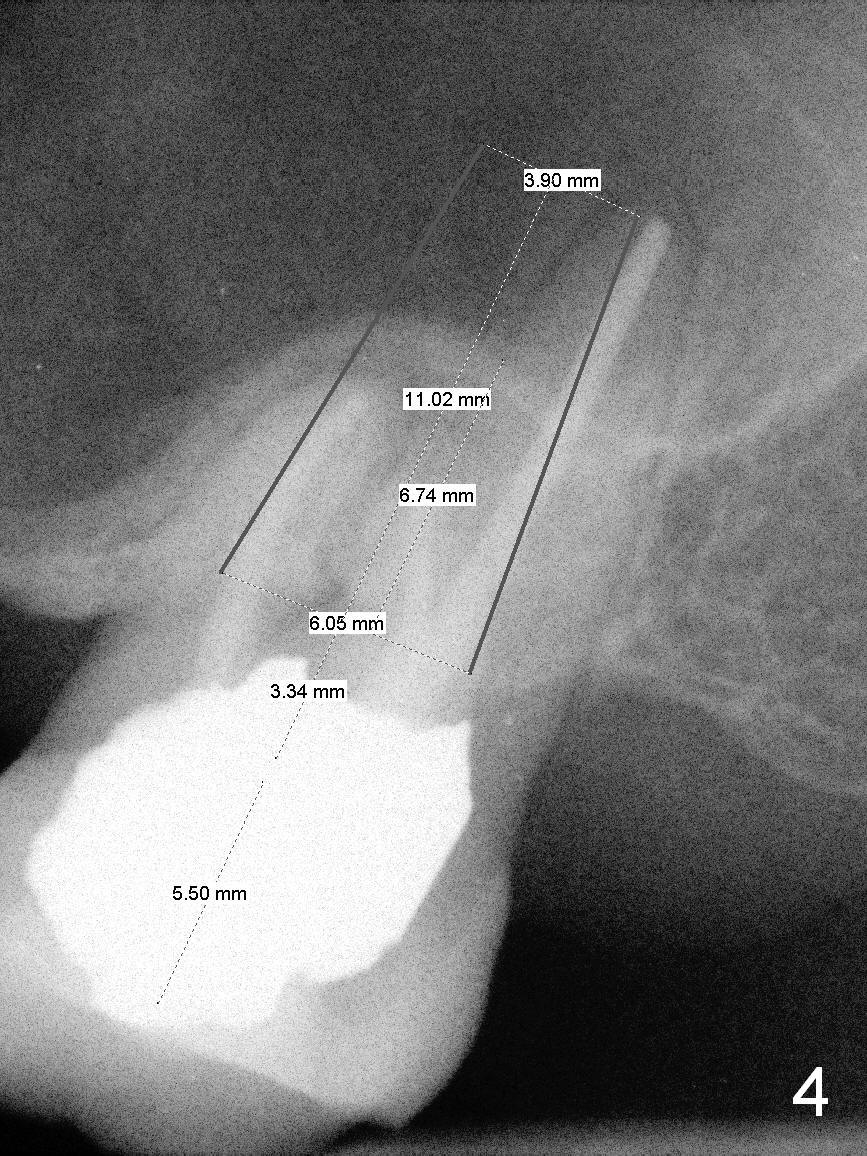

A 60-year-old man requests implant at #15, since the tooth with distal subgingival caries has kept fracturing in the last 4 years (Fig.1,2). Metronidazole will be used for socket disinfection. Since the socket is most likely large and single (fused roots), a large IBS implant (Fig.3,4: 6 or 6.5x9 or 11 mm) is to be placed following initial 7 mm depth of drilling or bone expansion (Fig.4). Prepare bone graft for sinus lift and gap closure. His bone is soft at #10; underprep is necessary at #15. An abutment is expected to be 6x4(3) mm (Fig.4). Since he is partially edentulous, an immediate provisional should be large enough to close the socket, but small enough not to be interfered with the partial denture on and off. Take photos of #10 to show no metal show.